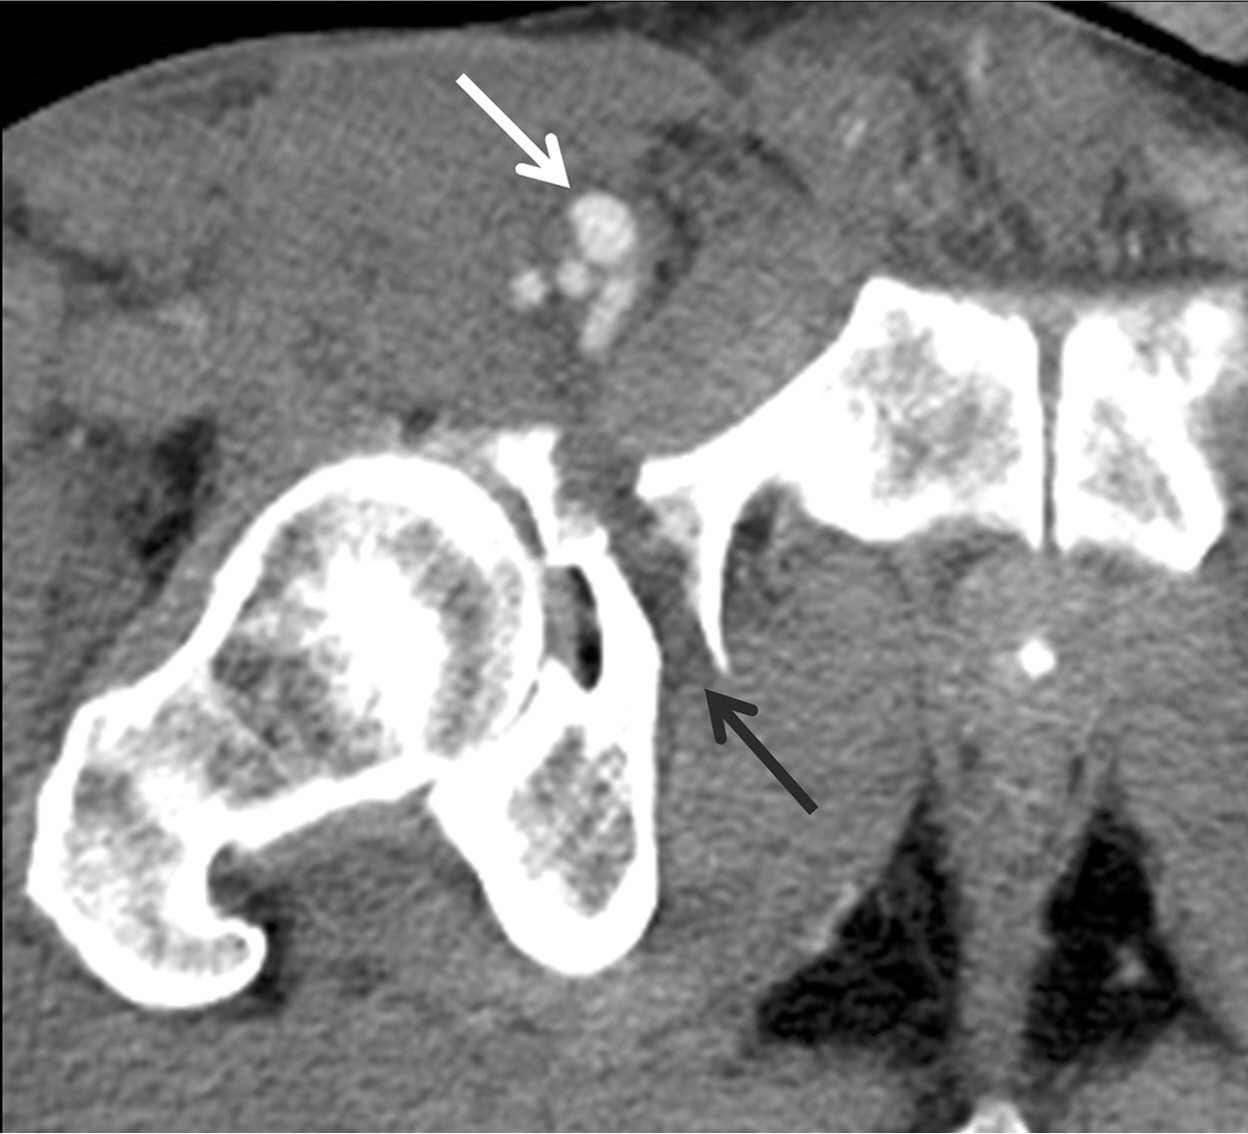

Fig. 1.

Fig. 1. The axial CT image shows a 1.2 cm-sized pseudoaneurysm at the right superficial femoral artery (white arrow). Note the fracture in the right anterior acetabulum (black arrow).